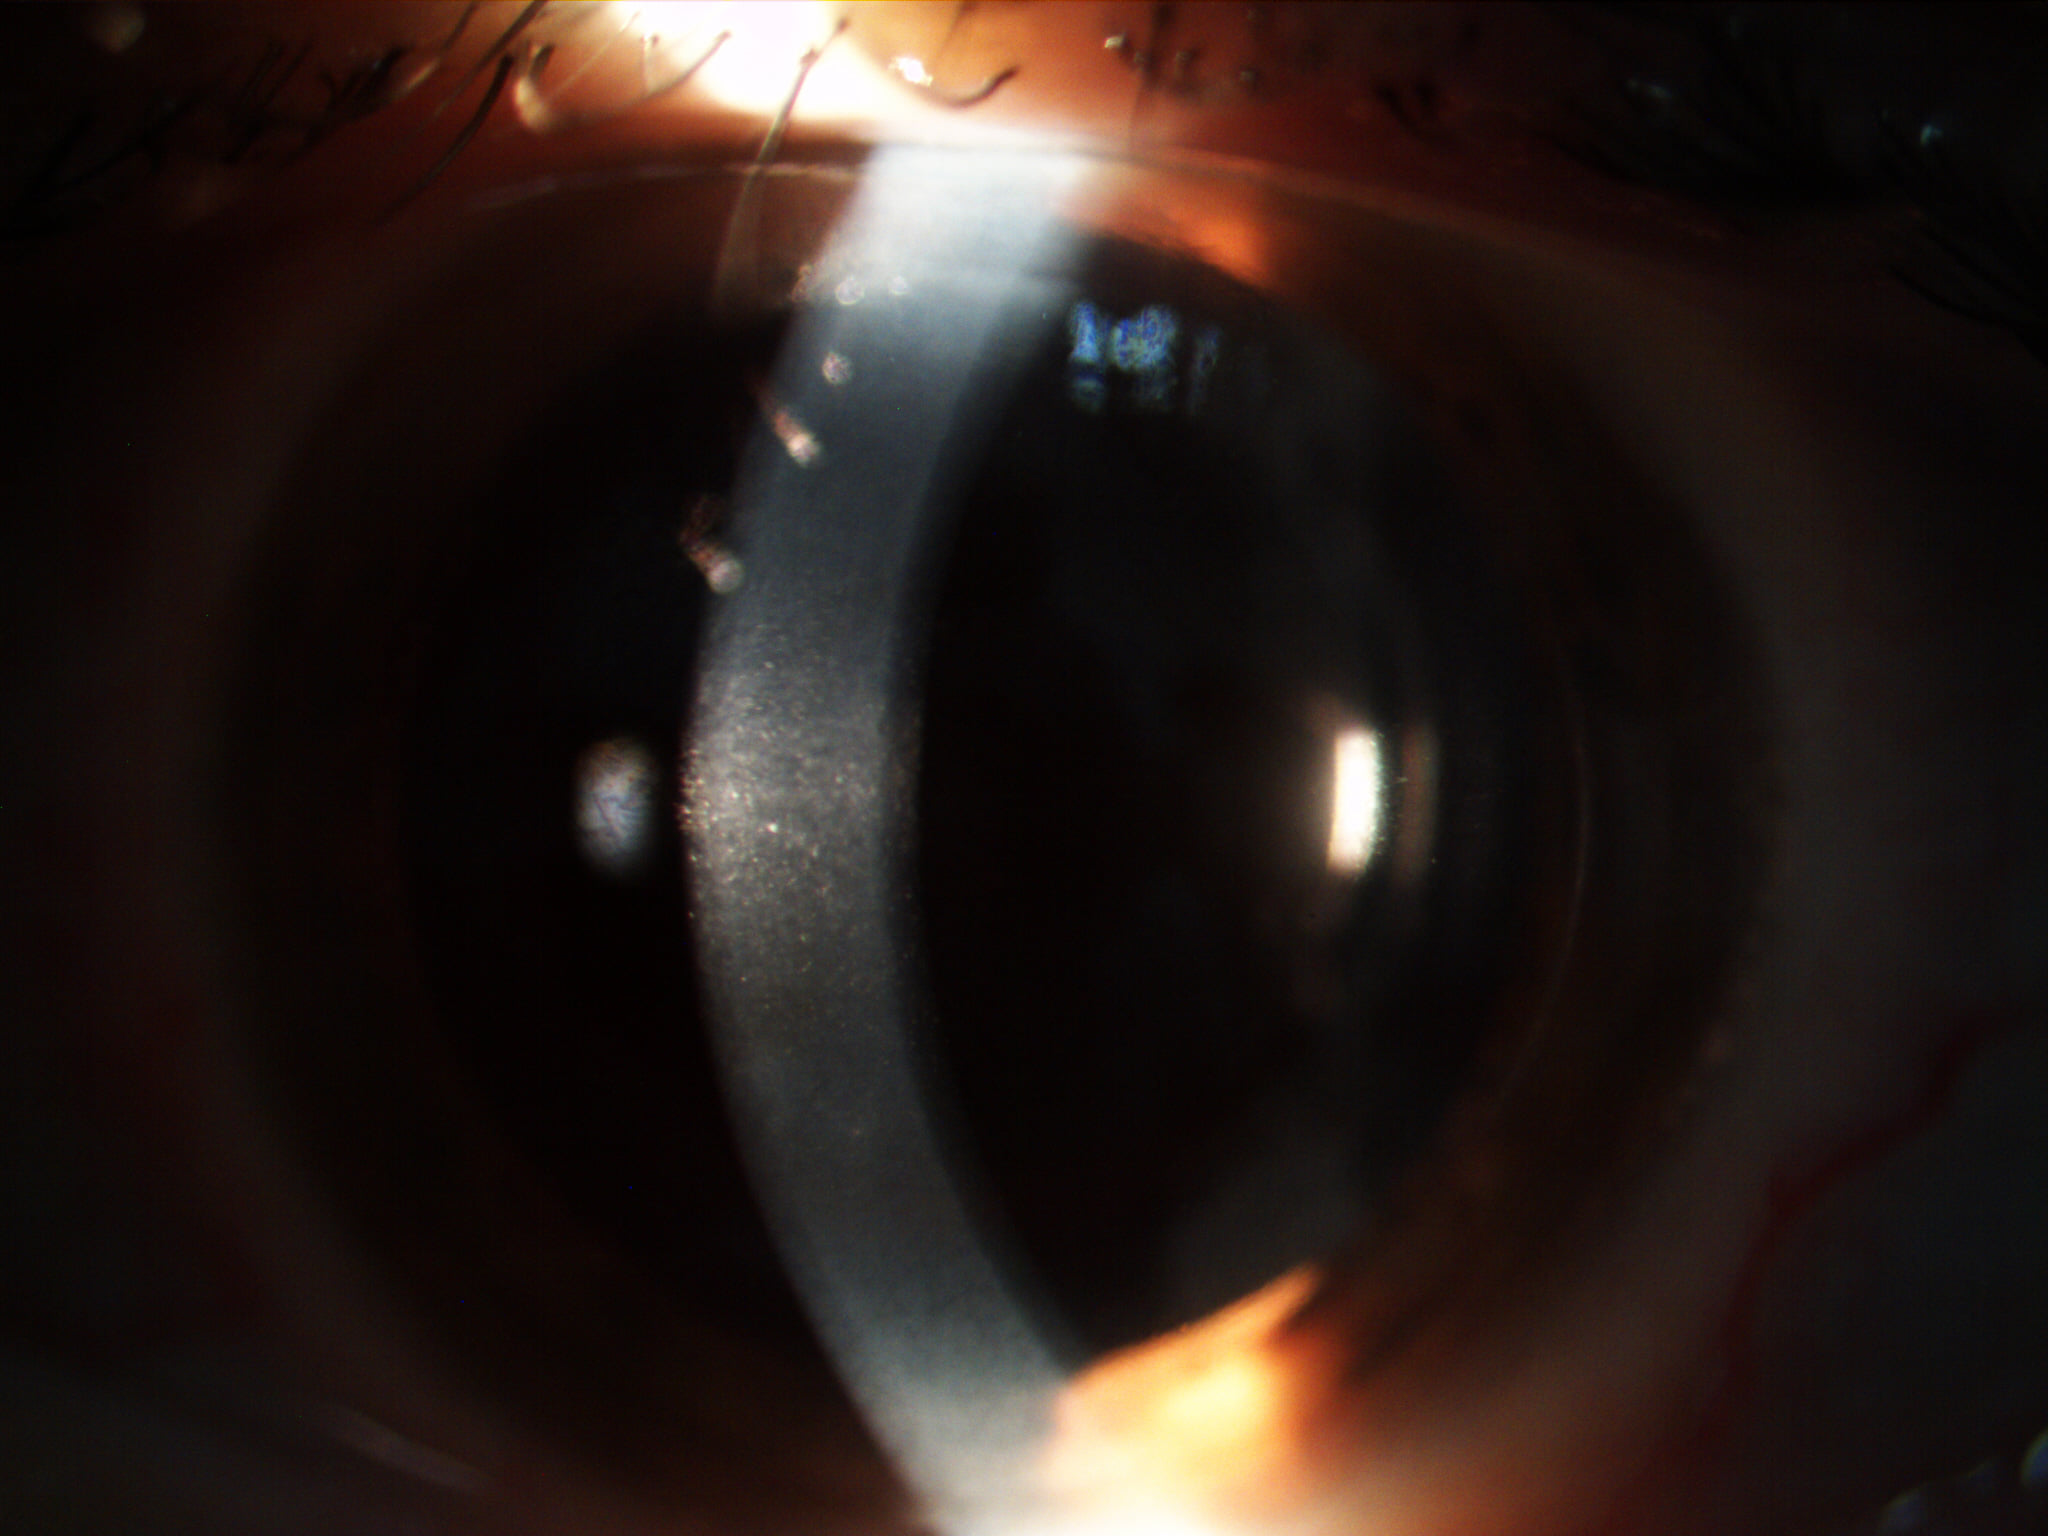

Mai jos, fotografii ale mai multor pacienti de-ai nostri cu Corneea Guttatta în faze medii, sau chiar avansate, la care am efectuat doar operația de cataractă, în urma căreia corneea a „supraviețuit” cu brio și nu a mai fost nevoie – cel puțin până acum – de un trasplant de cornee.